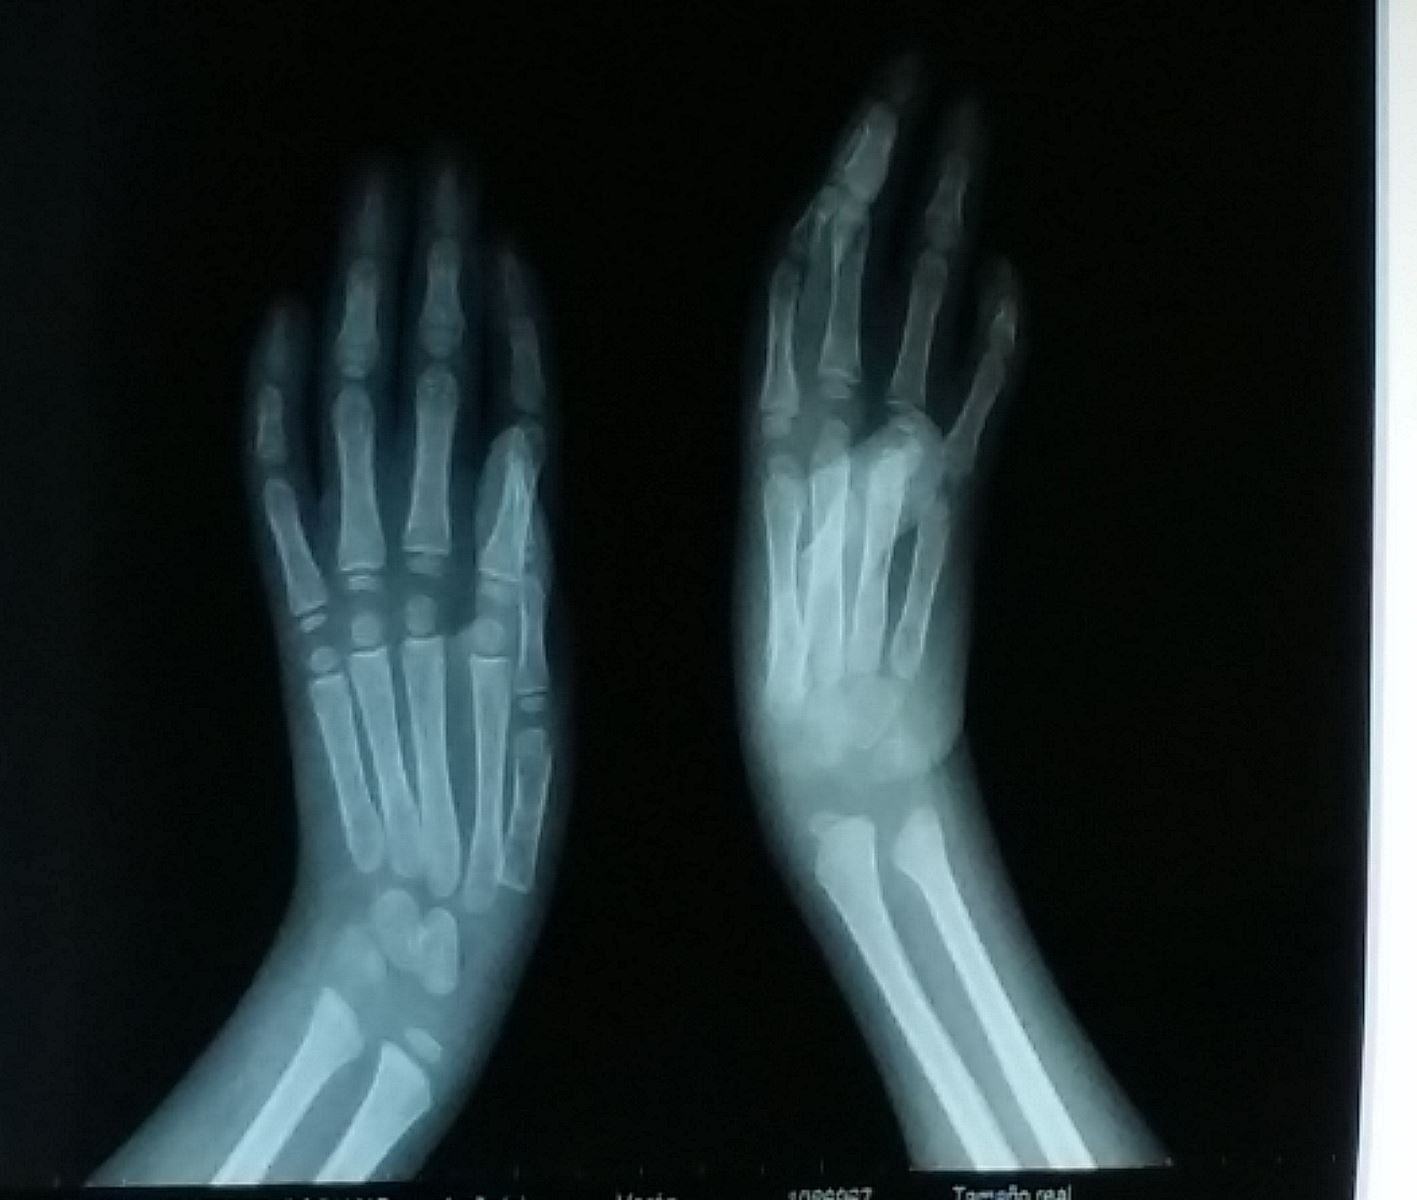

Engel has decreased ability to extend his left wrist due to congenital joint stiffness and muscle weakness. Surgery chosen for Engel was a dorsal carpal wedge osteotomy to improve his left wrist extension for functional tasks. He was placed in a cast post op. Therapy was continued for his right UE while in the hospital. Engel was used to fine motor and reaching during play therapy. Engel told the therapist that he liked the stretchy ball because he could stretch it like the therapists stretched him. He had a very large vocabulary for only 3 years old, not unusual for children with arthrogryposis.